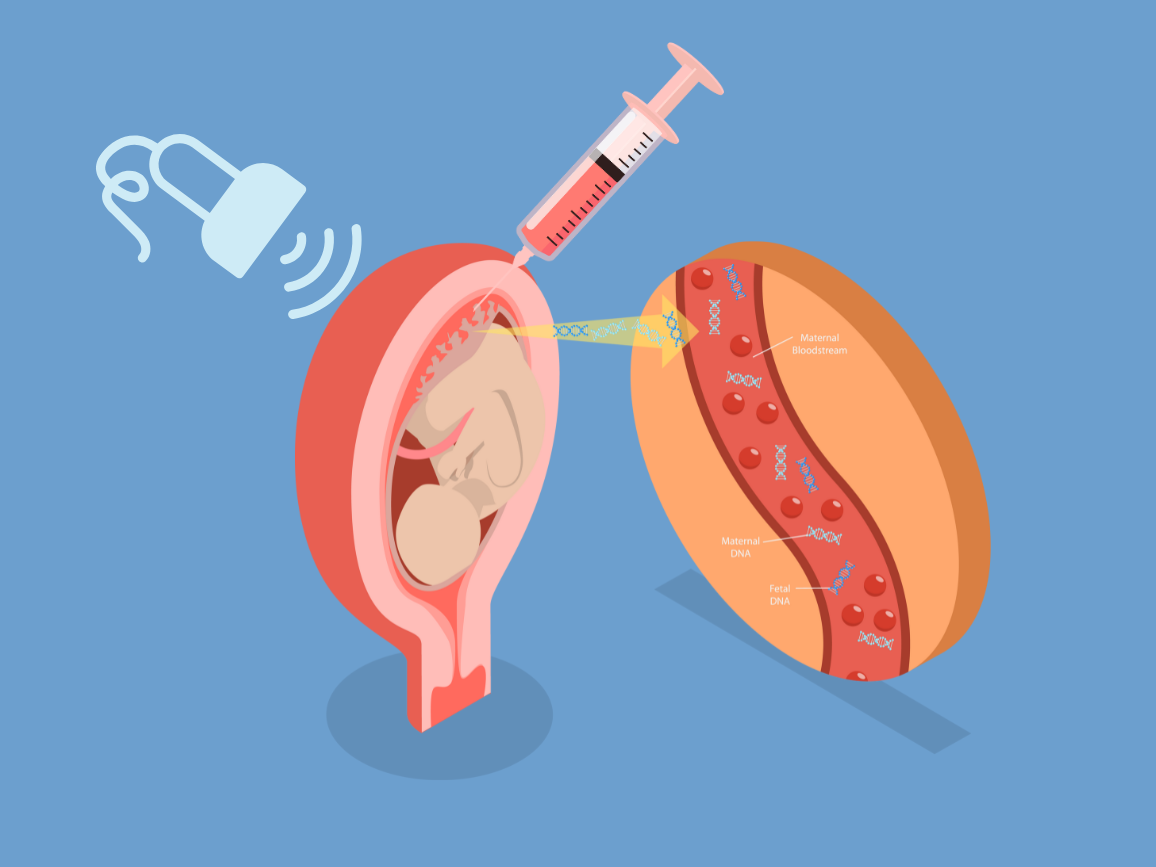

1. Amniocentesis

Amniocentesis involves collecting a small sample of amniotic fluid that surrounds the baby in the womb. It helps detect chromosomal and genetic conditions, such as Down syndrome and neural tube defects, with high accuracy. The procedure is performed under continuous ultrasound guidance to ensure safety.

3. Fetal Blood Sampling

Also known as cordocentesis, this test involves drawing a small sample of fetal blood from the umbilical cord to check for fetal anemia, infections, or chromosomal abnormalities. It is typically performed when earlier tests are inconclusive or when a more detailed genetic or hematologic study is needed.